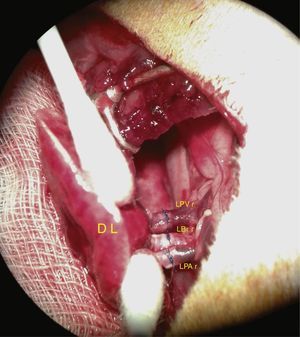

Preparation of the GraftWhen the lung block has been extracted, the left lung must be separated, clamping the bronchus to keep it inflated. The bronchus, the artery and the pulmonary veins are dissected as distally as possible to the lung to assist anastomosis (Fig. 1).

Extraction and preparation of the donor lung. Median sternotomy and dissection and extraction of the heart–lung block. Dissection of the left pulmonary artery (LPA), left pulmonary veins (LPV), and the left bronchus (LBr). AO: thoracic aorta; IVC: inferior vena cava; LA: left atrium; L SVC: left superior vena cava; LL: left left; RA: right atrium; R SVC: right superior vena cava.